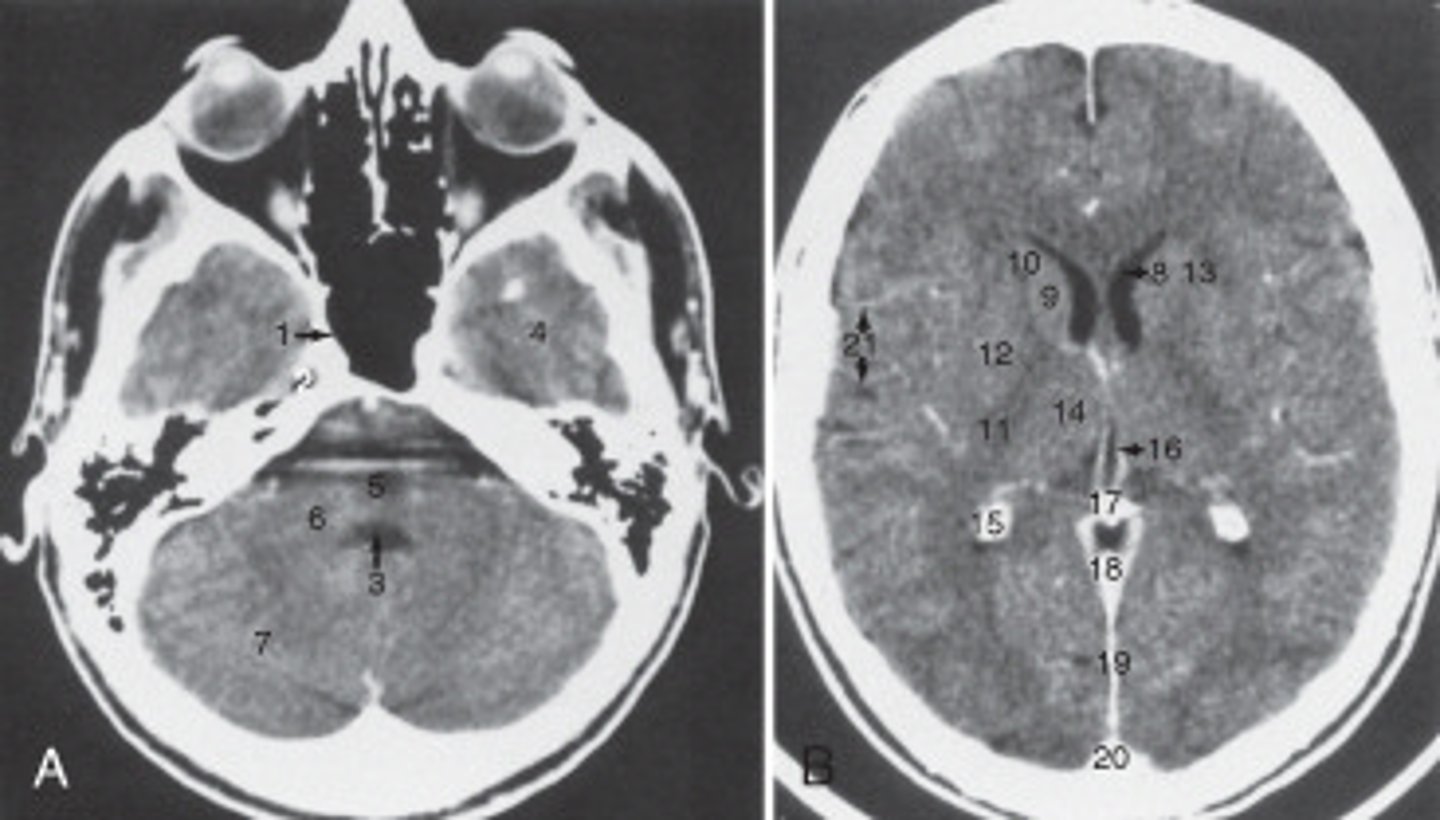

The anterior (frontal) horn of the lateral ventricle is labeled as:

<p>The anterior (frontal) horn of the lateral ventricle is labeled as:</p>

The sphenoid sinus is labeled:

<p>The sphenoid sinus is labeled:</p>

The thalamus is labeled:

<p>The thalamus is labeled:</p>

the fall cerebri is labeled:

<p>the fall cerebri is labeled:</p>

The structure labeled 15 is the:

<p>The structure labeled 15 is the:</p>

The structure labeled 3 is the:

<p>The structure labeled 3 is the:</p>

The structure labeled as 7 is the:

<p>The structure labeled as 7 is the:</p>